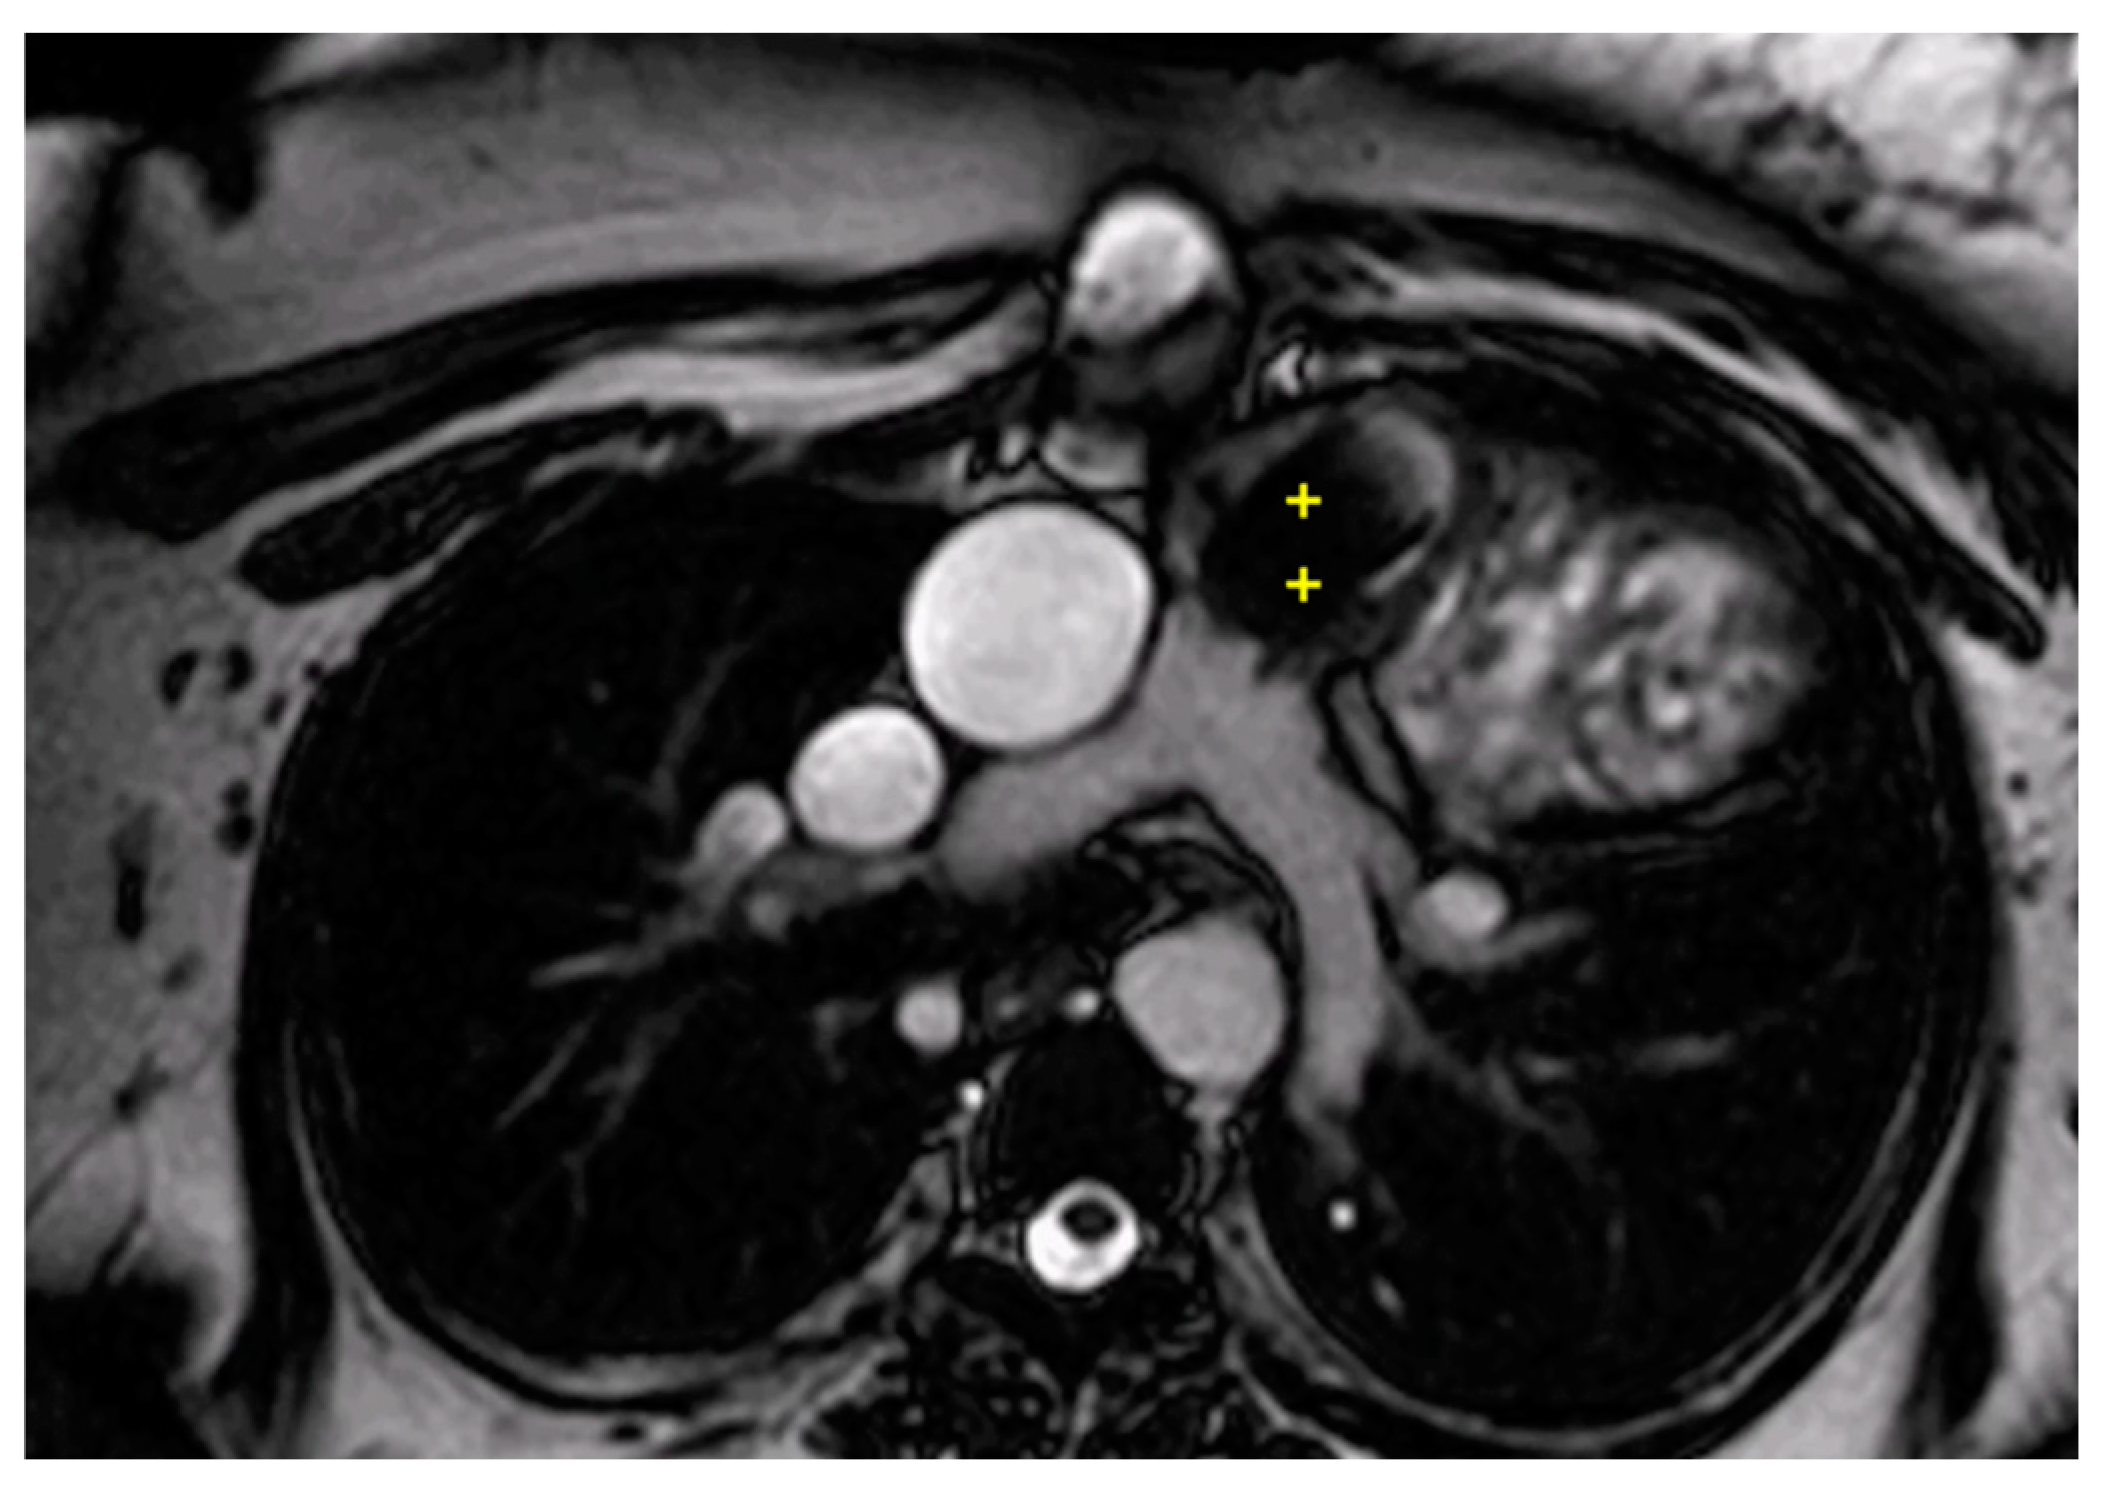

Figure 6.

Cine bSSFP image from a 15-year-old male with TOF, post complete correction and Melody valve implantation. The image shows significant migration of the Melody valve into the infundibulum (++).